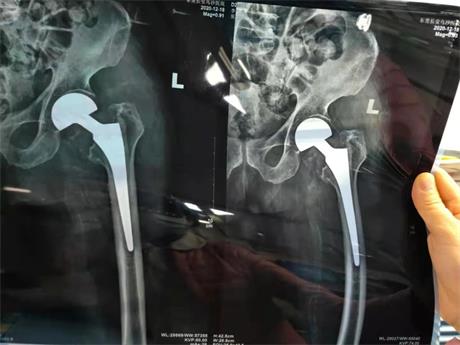

高龄患者骨质疏松,无法实施常规骨折固定术,进行人工股骨头置换手 术是蕞佳方案。缜密制定手 术方案后,一星期后的12月16日上午9点45分,骨科团队对李爷爷着手实施“左股骨颈骨折切开+人工股骨头置换术”,麻 醉师吴月英行腰硬联合麻 醉,谢忠存主任、赵子涵医师主刀。术中切开关节囊后可见左股骨颈骨折,情况比较复杂。谢主任耐心细致操作,完整取出股骨头,清理好骨折端碎骨块及血凝块后,安装股骨水泥型假体,待骨水泥凝固后再安装股骨头假体,复位髋关节。活动髋关节,发现屈曲、外展、外旋、内旋等各向活动不受限,达到满意效果,检查髋关节稳定无脱位,置入引流管后给予缝合。术前评估充分,术中配合娴熟,患者各项生命体征平稳,不到两小时手 术顺利完成,患者被推回病房接受后续治 疗。

外二科团队手 术资料图